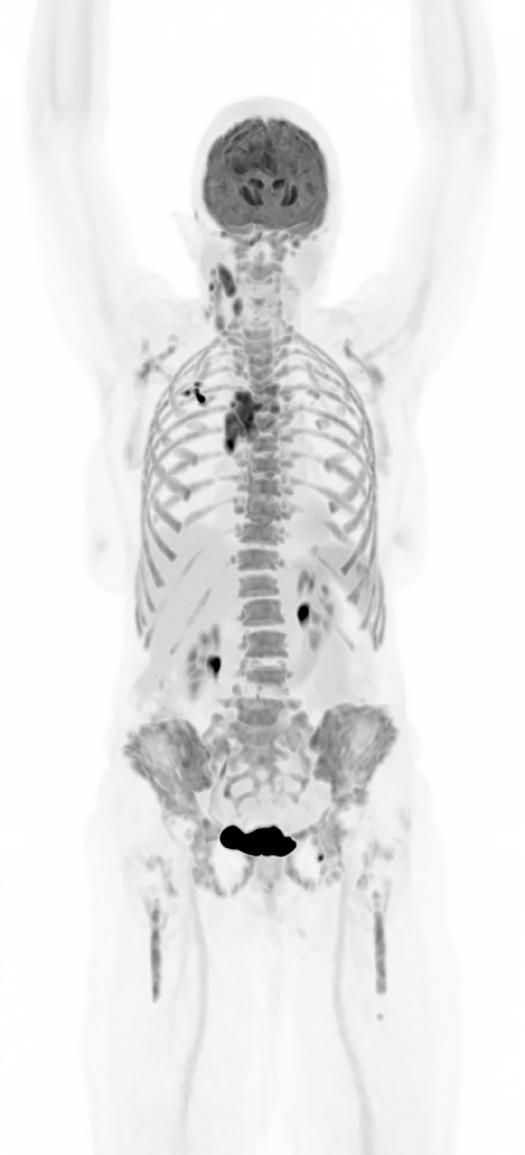

The Whole Picture: Total-Body PET and the Future of Biopharma

What if a clinical scan could transform biopharmaceutical innovation and patient care, streamlining drug development, clinical trials, and complex disease diagnosis? Total-body Positron Emission Tomography (PET) imaging is turning that vision into reality, offering a full-body, real-time view of human physiology.

Total-body PET is redefining what is possible in molecular imaging and biopharmaceutical development. This advanced PET technology can deliver full-body scans in minutes, with a sensitivity of up to 40x greater than conventional standard field PET scanners1 and potential for significantly lower radiation exposure. This opens exciting new avenues for research and discovery. It enables clinicians to study disease in real time across the whole body, revolutionising how we diagnose, stage and treat complex conditions like cancer, cardiovascular disease and neurodegenerative disorders. For patients, this means faster scans and earlier interventions, with the opportunity for more personalised treatments. For research and industry, it unlocks a powerful new platform for evaluating novel therapies, tracking their behaviour and accelerating their path to market.

But realising the full potential of total-body PET requires more than cutting-edge scanners. It demands a robust infrastructure, one that includes a reliable supply of radiotracers and an integrated framework for data sharing and collaboration. In the UK, the National PET Imaging Platform (NPIP) is building exactly that. What it reveals is not just a clearer image of the body, but a blueprint for the future of biopharmaceutical development.

Continued technological advances in hardware and software have led to a new generation of PET scanners with far greater sensitivity and resolution. While conventional PET relies on multiple bed positions and generating multiple images to acquire

a whole picture of the body, total-body PET has a field of view wide enough to take an image from head to toe in a single scan, and a detector capable of 40x higher sensitivity.¹ This means the whole body can be imaged faster, at higher resolution and in real-time. It also means lower doses of radiotracer are required to generate the same amount of detail (Table 1).1,3

Feature

Conventional PET Total-Body PET

Large Axial Field of View (LAFOV) 15–20cm >100cm*

Sensitivity Moderate Ultra-high (up to 40x higher for whole-body images)

Average Total-Body scan time** 10–30 min 30 seconds–3 minutes

Average radiation dose for a full-body scan** ~370 MBq ~9.25 MBq

Dynamic imaging potential (continuous capture of data over time)

Patient throughput

Tracers can be followed for ~3 half-lives, limiting dynamic imaging

Lower

Tracers can be followed for 5–6 additional half-lives, enabling whole-body, real-time imaging

Potential for twice as many clinical scans per day

*Scanners in the NPIP network have a LAFOV of between 106–194cm. **Based on (18F)-FDG scan procedures.

Table 1. Differences between conventional PET scanners and total-body PET scanners.1,4,5,6

Importantly, total-body PET does not replace conventional PET imaging. Conventional PET remains indispensable in clinical practice, especially when imaging needs are localised to a specific area of the body. But for complex diseases that span multiple organ systems or in cases where lower doses of radiation are required, total-body PET offers a transformative new lens: